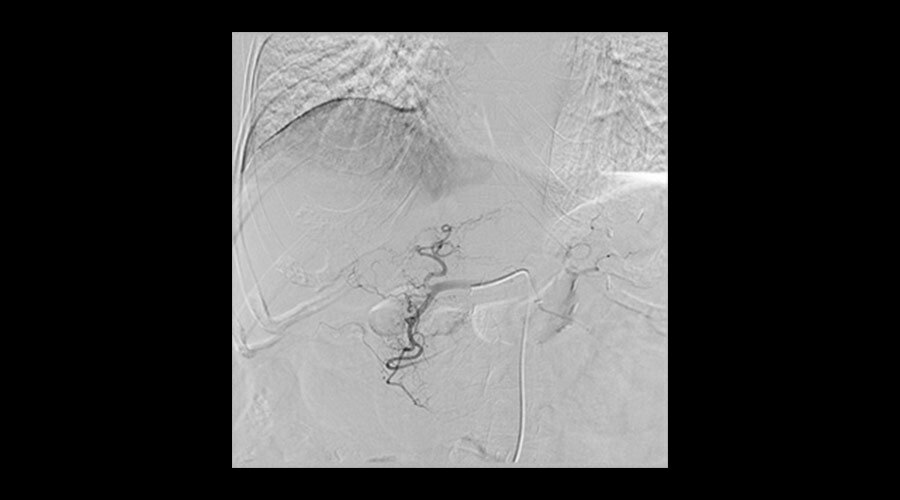

Klinik Görüntüler

-

İliyak stentlemesi